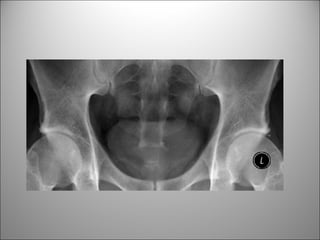

HUESOS

CALCIFICACIONES Y ARTEFACTOS